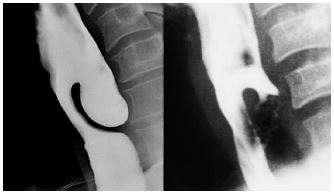

- Always consider the possibility of a pharyngeal pouch

(Zenker’s diverticulum) which is easily perforated (Figures

30, 31)

- A pharyngeal pouch is located immediately behind the upper oesophageal sphincter

- Finding the oesophageal lumen may be very challenging

- A scope will always automatically enter a pouch